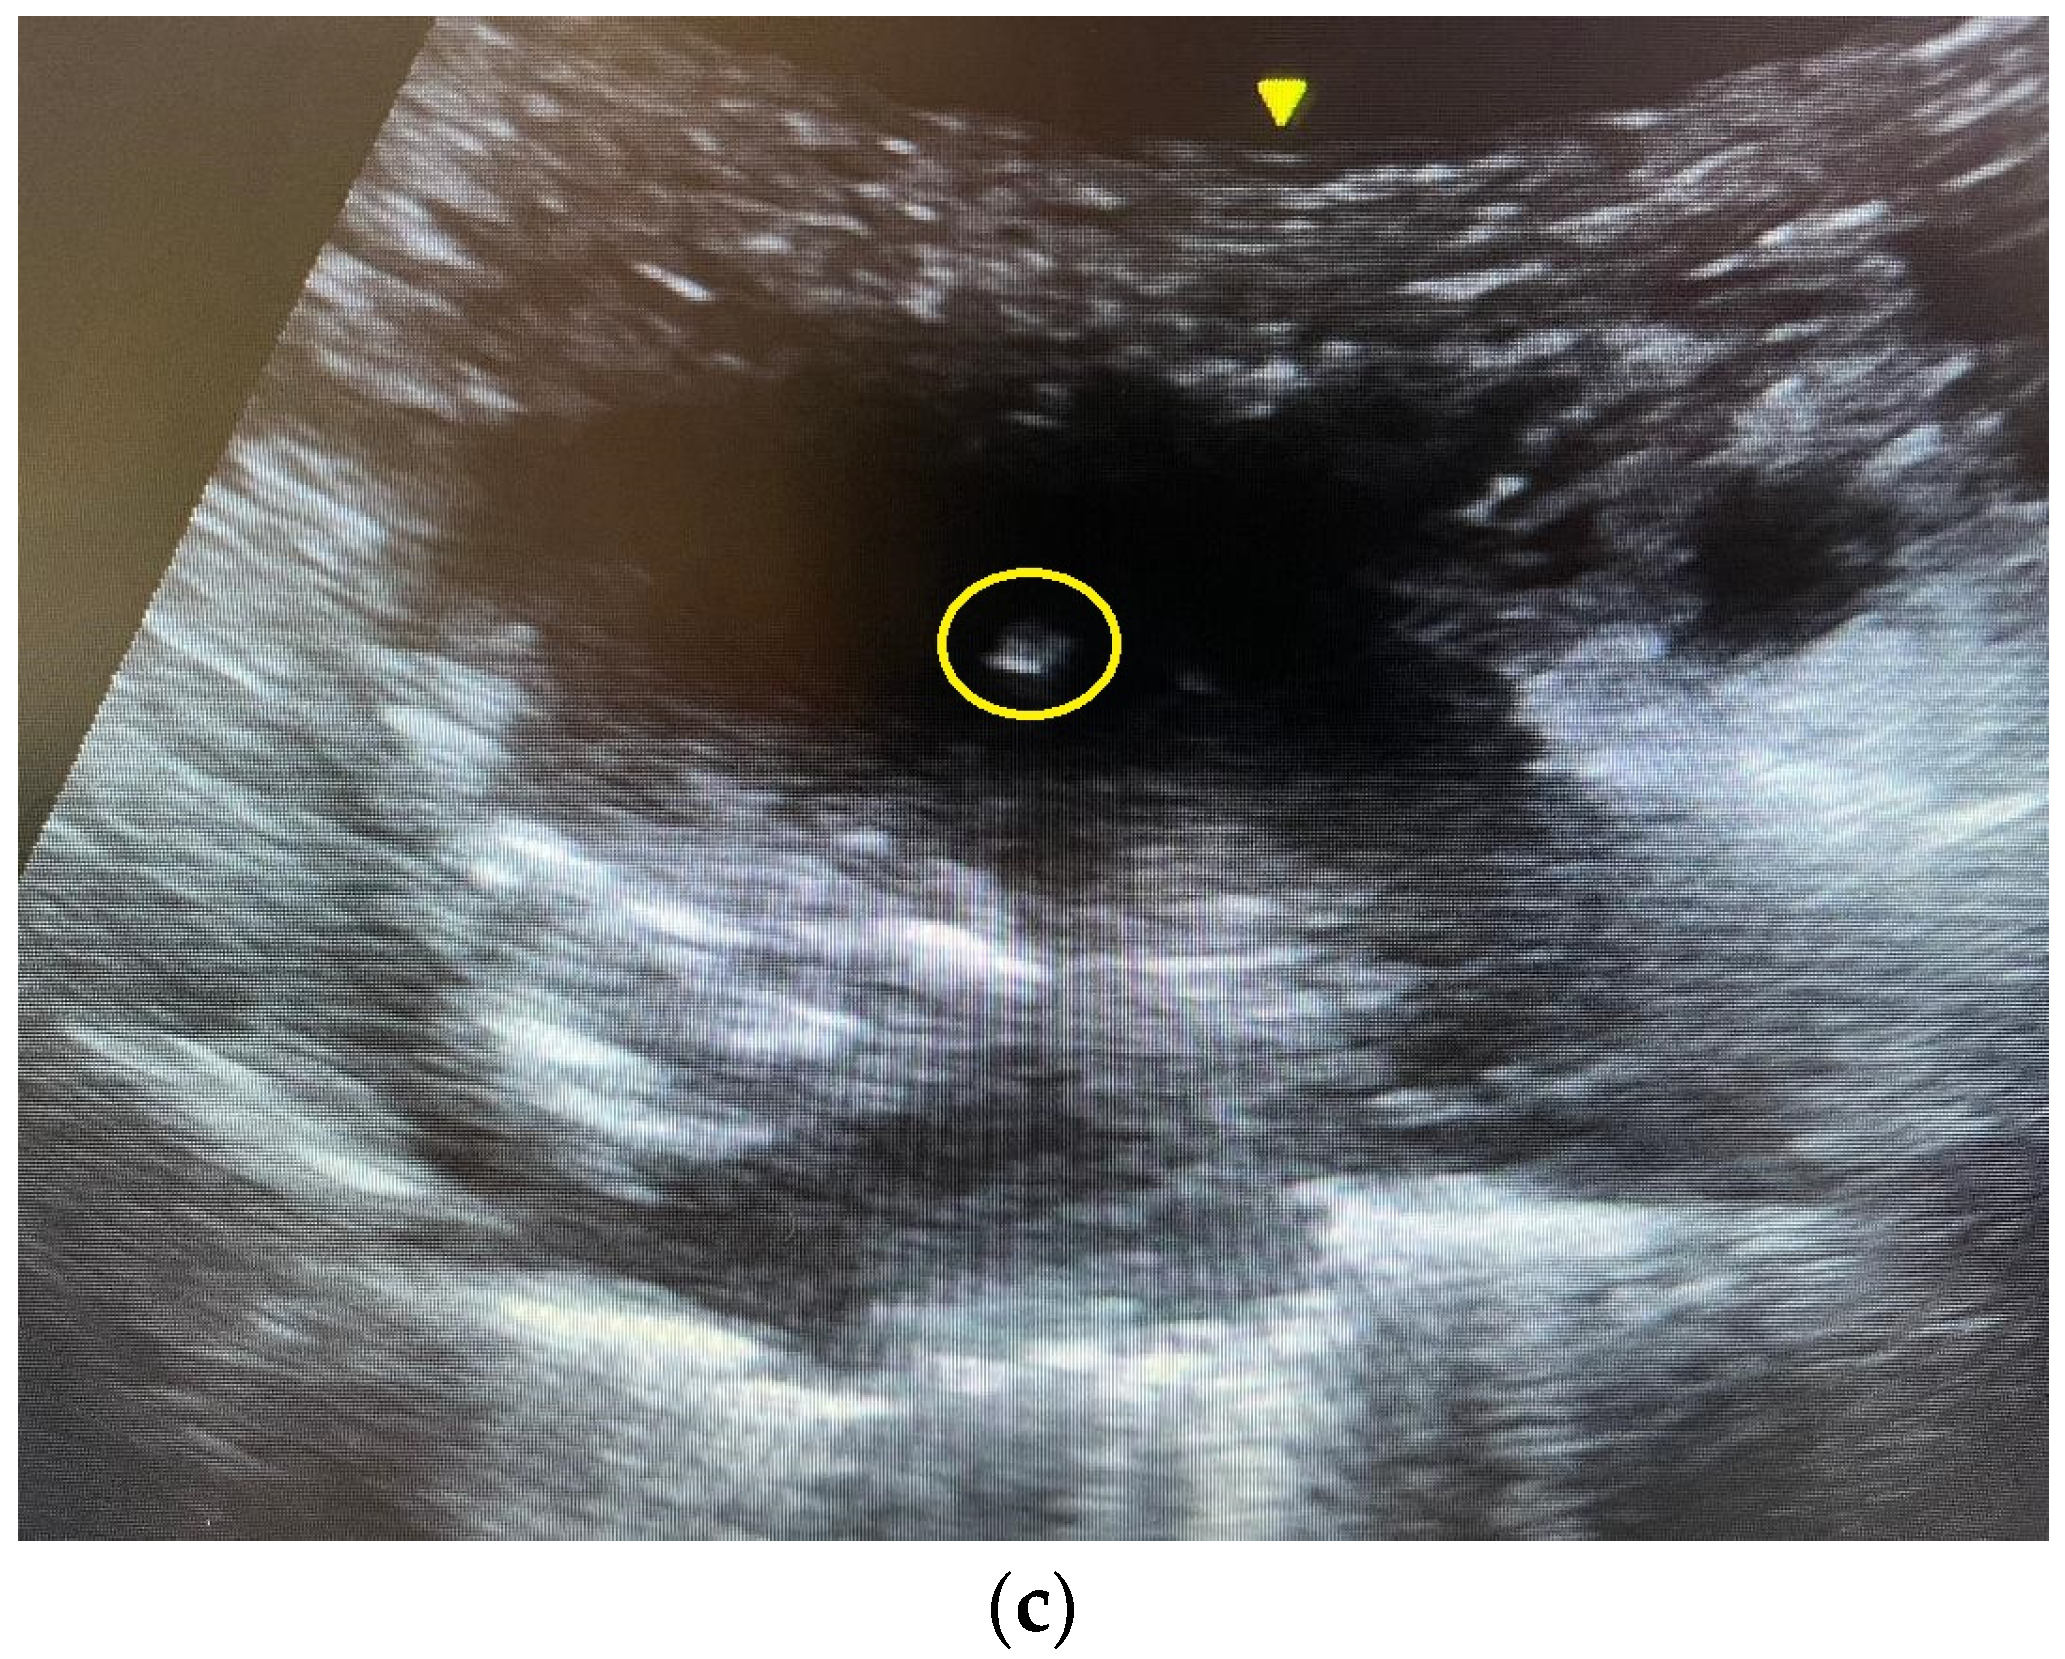

2.4. The Ultrasound-Guided Fine-Needle Aspiration